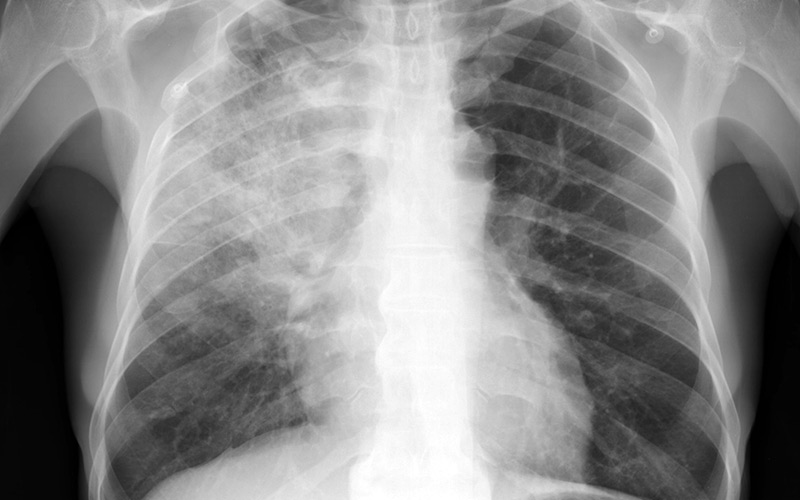

Публикуем актуальную статистику по зараженным пневмонией в стране.

На 9 августа 2021 года пневмония была диагностирована у 457 человек, в результате чего общее количество заболевших достигло 15399 человек, сообщает Минздрав.

Вчера 584 из них выздоровели. Общее количество выздоровевших достигло 8121.

Кроме того, 4 пациента умерли. Всего в республике от пневмонии умерли 103 человека.